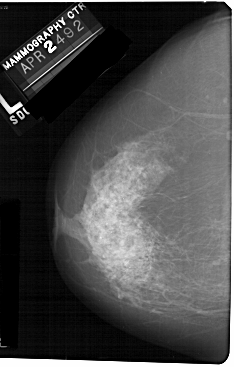

A_1127_1.LEFT_CC

LEFT_CC LINES 5491 PIXELS_PER_LINE 3496 BITS_PER_PIXEL 12 RESOLUTION 43.5 NON_OVERLAY